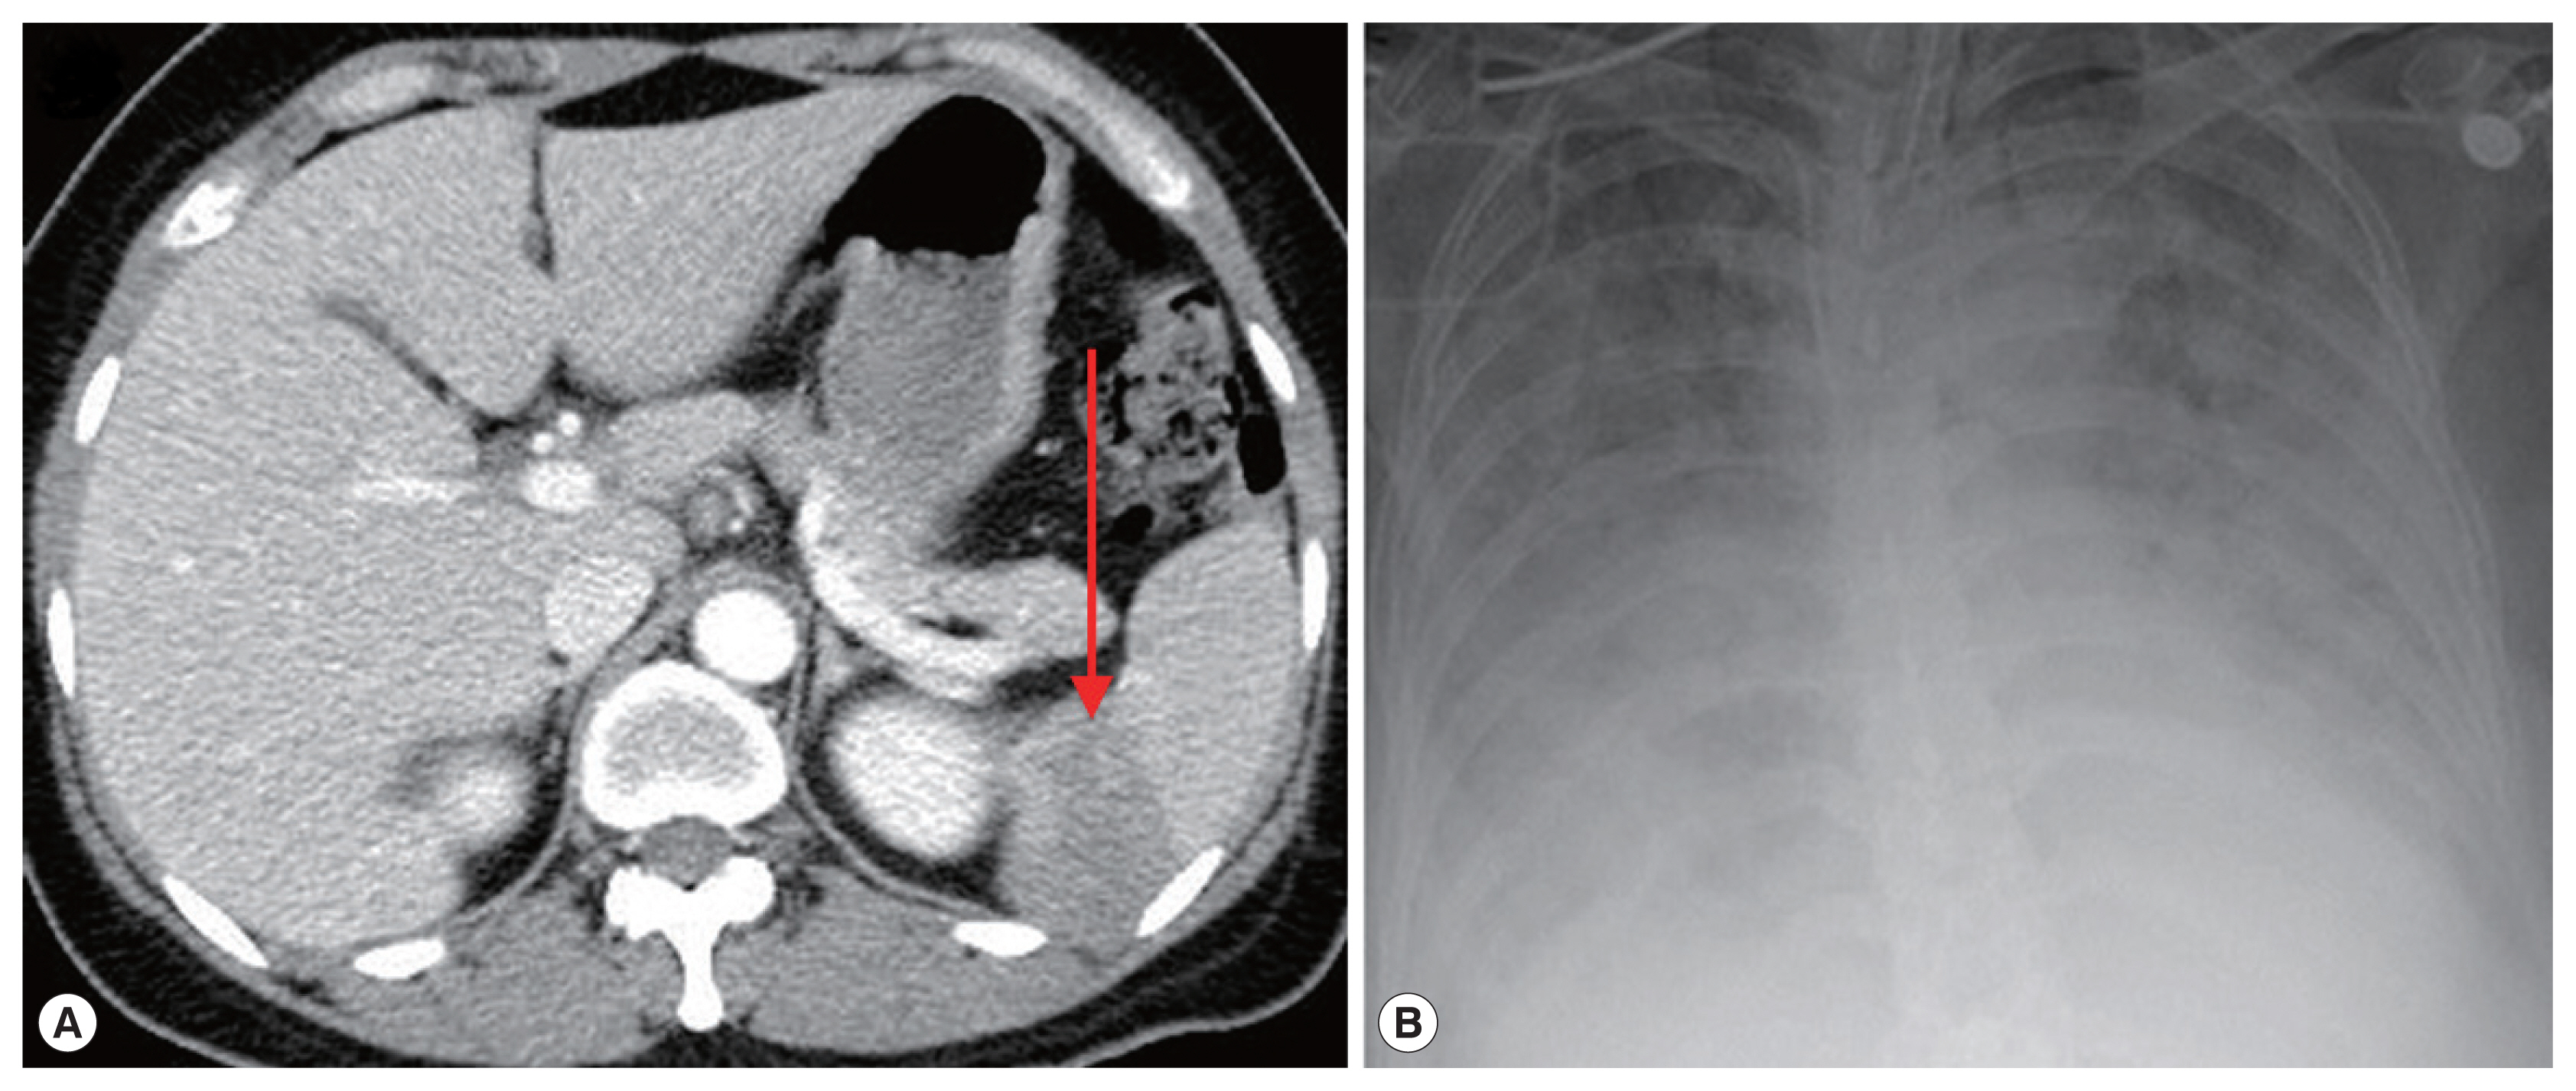

On admission, her vital signs were: blood pressure 148/73 mmHg, heart rate 120 beats per minute, respiratory rate 18 breaths per minute, and body temperature 40.7°C. Laboratory examination showed white blood cells 5,610 cells/μl (normal range 4,000–10,000 cells/μl), hemoglobin 11.2 g/dl (normal range 12.0–15.3 g/dl), platelets 53,000 cells/μl (normal range 150,000–400,000 cells/μl), erythrocyte sedimentation rate 69 mm/hr (normal range 1–22 mm/hr), and C-reactive protein 9.52 mg/dl (normal range 0.0–0.3 mg/dl). Blood smear showed erythrocyte-containing organisms suspicious for Plasmodium species (Fig. 1). Abdomen-pelvis computed tomography revealed findings consistent with splenic infarction.

A 72-year-old woman without underlying disease visited our hospital for a fever that started 2 weeks before. She had been in Boston in the United States for 2 months previously. Vital signs were: blood pressure 93/67 mmHg, heart rate 76 beats per minute, respiratory rate 18 breaths per minute, and body temperature 37.7°C. Laboratory findings showed white blood cells 5,480 cells/μl, hemoglobin 10.8 g/dl, platelets 52,000 cells/μl, erythrocyte sedimentation rate 105 mm/hr, and C-reactive protein 15.1 mg/dl. Malaria-like organisms were seen on the observation of blood smear; however, the malaria antigen test was negative. When the blood smear morphology was closely observed, Maltese cross forms were visible in the red blood cells; therefore, babesiosis was diagnosed (Fig. 1B). Atovaquone 250 mg/proguanil 100 mg and azithromycin 500 mg were prescribed. However, fever persisted, and she developed pulmonary congestion. On diagnosis of severe babesiosis, we switched the medication to quinine and clindamycin, and red blood cell exchange was performed. As pulmonary congestion exacerbated, she was intubated due to respiratory failure (Fig. 2B). Doxycycline therapy was prescribed for possible coinfection with Borrelia or Anaplasma species.